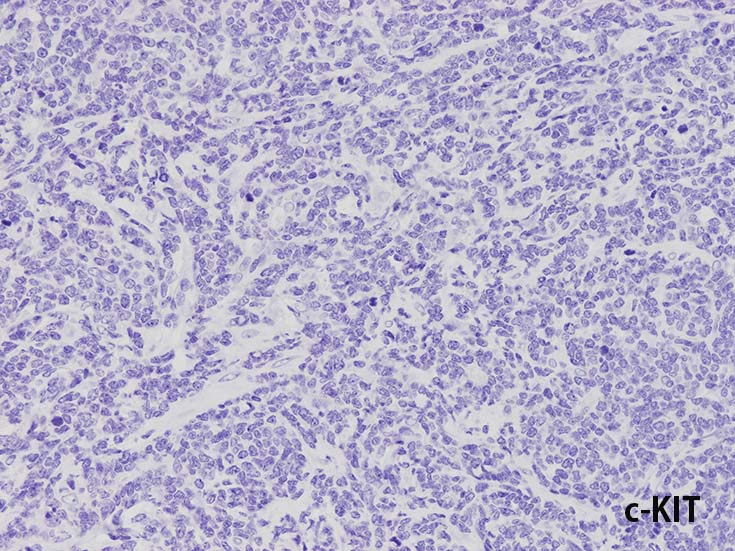

c-KIT(CD117)

- まれにc-KIT(CD117)+; FLT3の活性化変異に関連する.